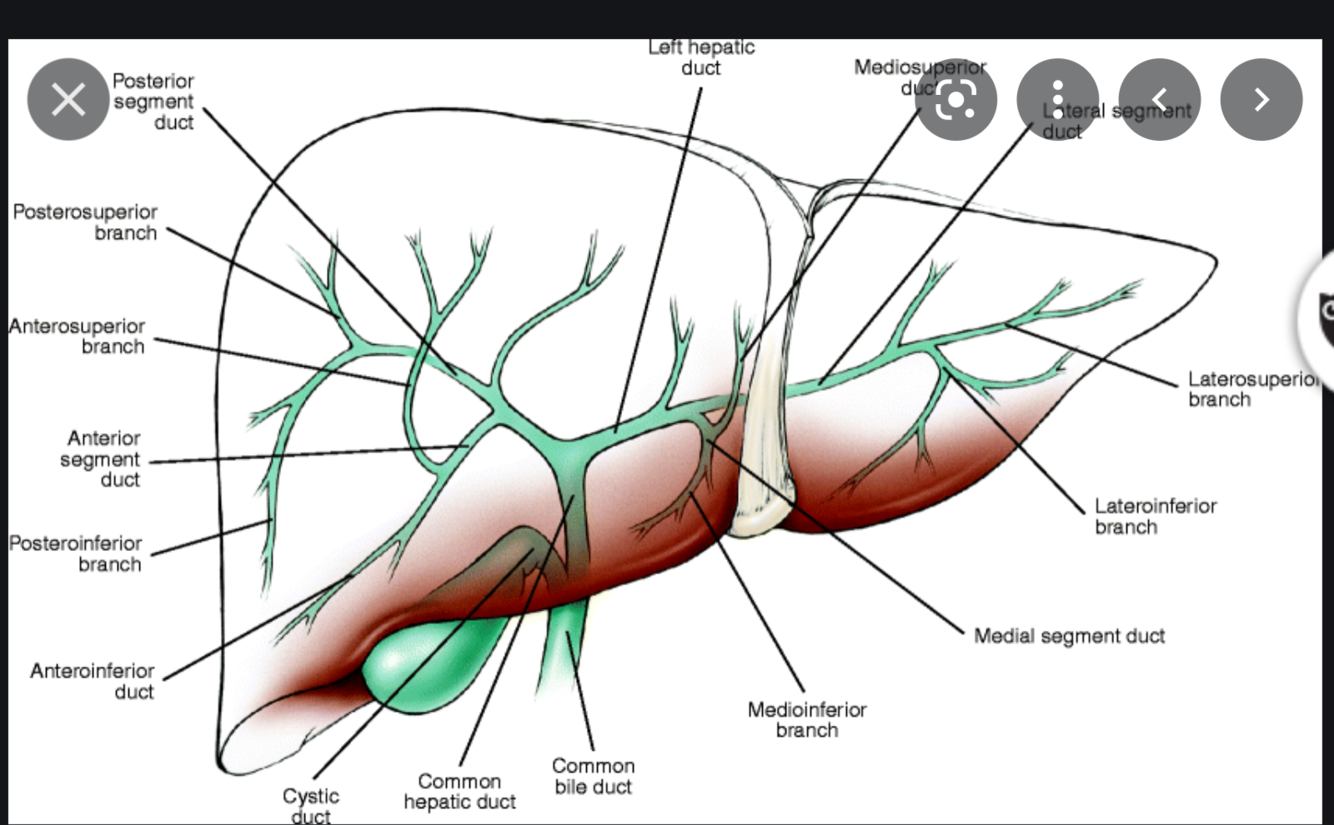

Name the Ductal anatomy

- Right Hepatic duct

- Right Anterior superior

- Right anterior inferior

- Right posterior superior

- right posterior inferior

- Caudate

- left hepatic duct

- left medial superior segment

- left lateral superior

- left medial inferior

- left lateral inferior

- the RHD and the LHD form the common hepatic duct (CHD) which receives the cystic duct from the GB to form the CBD.